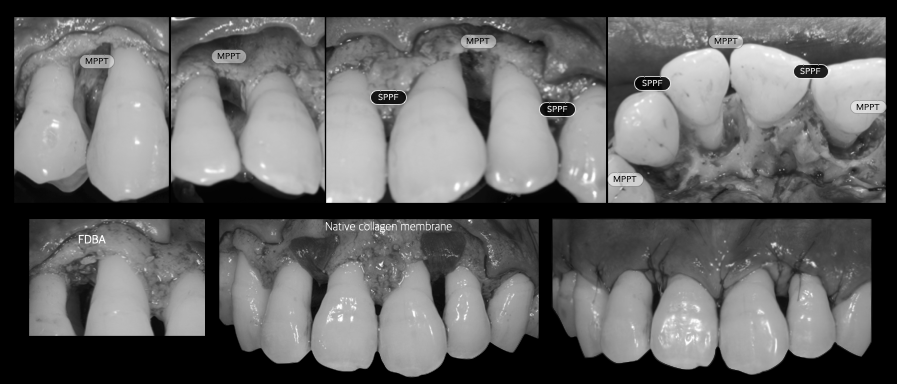

歯周組織再生療法

通常抜歯の対象となる歯であっても、歯周組織再生療法を行うことで残せる可能性はあります。もちろん、適応条件はありますが上記の精密な診査診断を行うことで、歯を残せるか否かを判断することが可能です。重度歯周病だから”必ず抜歯”ということはありません。

歯周外科、歯周組織再生療法

歯周基本治療では取り切れない場所にある歯石を取るために、歯茎を切開し、目に見える状態で処置をします。また適応であればエムドゲインやリグロスといった再生誘導材料を用いた歯周組織再生療法を行い、失った骨を再生させる治療を行います。

治療例

重度歯周病の症例